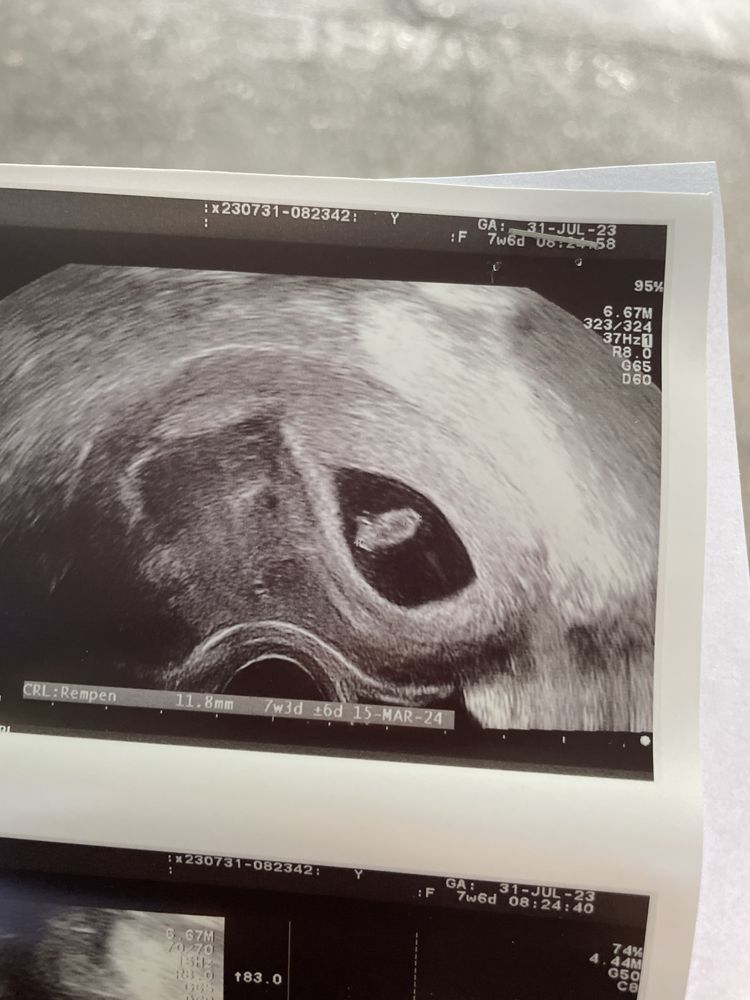

Кто расшифрует показатели по скринингу и пол малыша?🙈 Была сегодня на скрининге 🥹 срок по узи и месячным день в день. Пол сказала узистка даже смотреть не будет, как я не просила, сказала она мне терпеть 🥲 отправлю замерчики😁 правда они на укр языке. Посмотрите знающим глазом 😁🫂 и может кто по фото поймёт пол малыша, интерес берет своё

Добрый день, если есть узи на 7-8 неделе, то можно посмотреть по тесту Рамзи, на этом скрининге нужно смотреть под каким углом находится половой бугорок.

Настенька, ну по этому узи у вас девочка) Так как если фото узи перевернуть, то эмбрион будет слева, а слева по тесту Рамзи закреплены девочки, у меня совпало. Единственное у меня полукруг был вверху, а у вас на фото внизу, не знаю, зависит ли от него расположение эмбриона или нет.